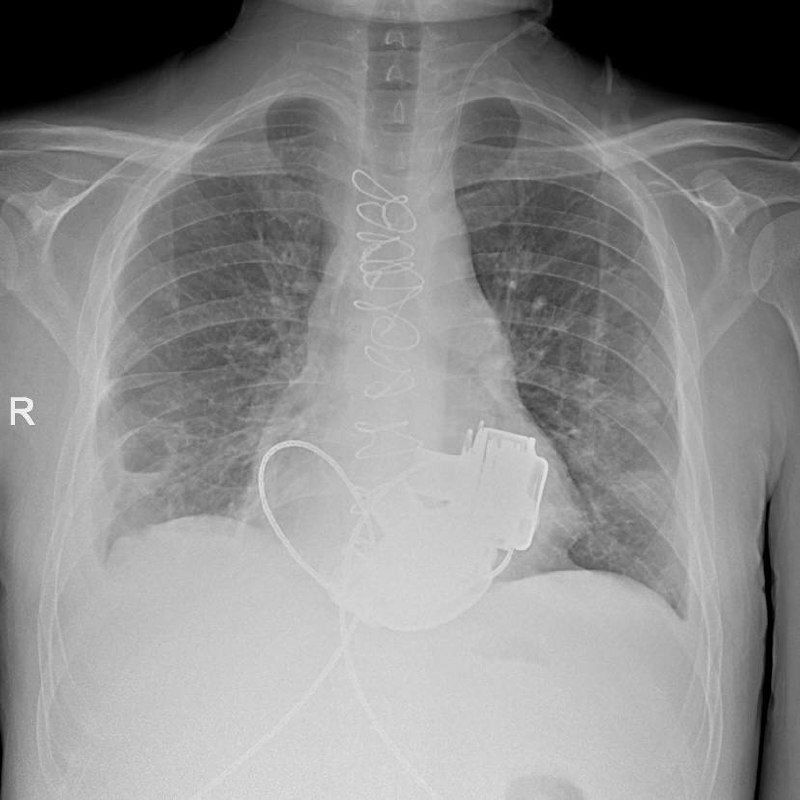

Как рассказали в пресс-службе комитета по здравоохранению Петербурга, в стационар Мариинской больницы 36-летний Антон поступил сразу с несколькими тяжелейшими диагнозами. Его показатели работы сердца были такими, будто человек уже не жив, а мёртв. Трансплантация сердца, которая показана в таких ситуациях, была невозможна из-за ряда осложнений. Тогда медики приняли решение провести непростое кардиохирургическое вмешательство – имплантацию искусственных желудочков. Обычно пациентам вживляют одно такое устройство, однако Антону потребовалось сразу два прибора. Потом пульс на запястье или шее у таких людей не прощупывается.

Послеоперационный период для мужчины был не простым, однако сейчас он уже научился жить с двумя приборами в теле и готов к выписке.

В региональном комздраве назвали имплантацию искусственных желудочков "мостиком" к трансплантации сердца. Пациент надеется, что вскоре сможет получить донорское сердце.